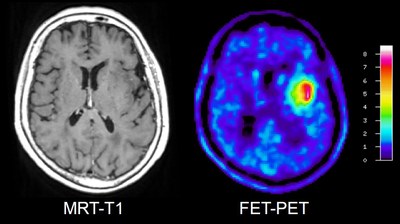

Der Hirntumor ist in der T1-gewichteten MRT nach Kontrastmittelgabe (links) nur sehr schwer abzugrenzen. In der FET-PET stellt sich der Tumor als stoffwechselaktives Areal dar (rot-gelbe Anfärbung).